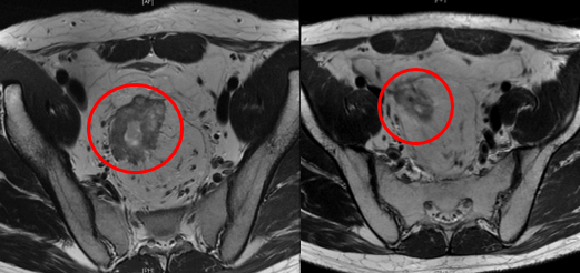

图3 患者治疗前后肿瘤对比。治疗后(右图红圈)较治疗前(左图红圈)肿瘤明显退缩。